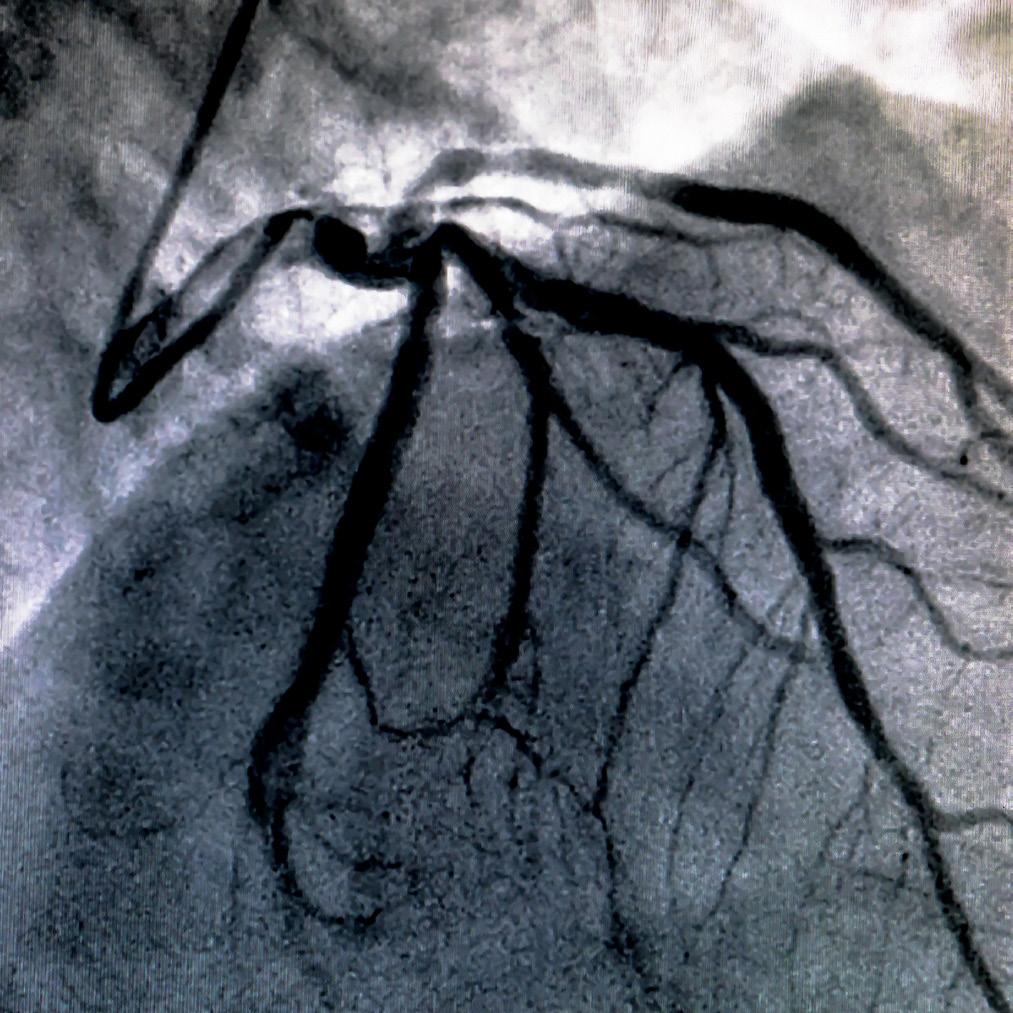

Imagem do famoso cateterismo cardíaco das artérias coronárias. Note como a artéria, após a injeção do contraste, fica “desenhada”, permitindo a visualização da anatomia e, consequentemente, de doenças que podem afetar esses vasos, tais como obstruções e anomalias.